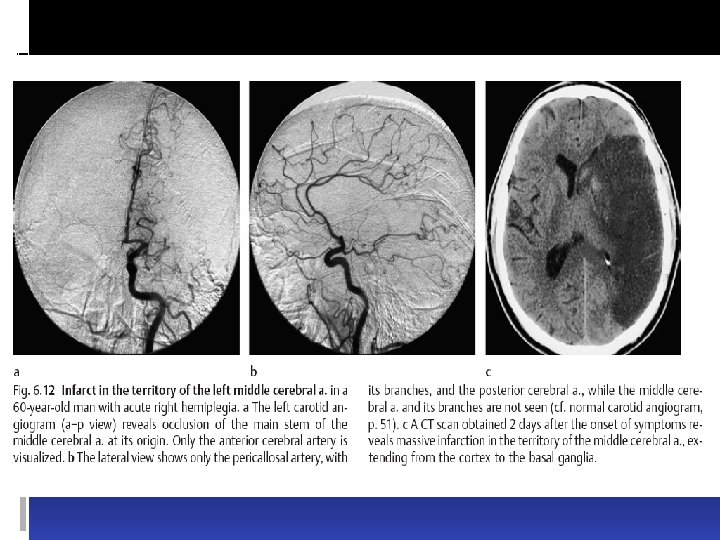

Types of infarct. There are three basic types of brain infarct, distinguished from each other by the caliber of the occluded arteries: Territorial infarcts are mainly produced by occlusions of the main trunks or major branches of cerebral arteries (cerebral macroangiopathy), which may be due to thrombosis, embolism, or other causes. The infarct includes both cortex and subcortical white matter and sometimes the basal ganglia and thalamus (Fig. 6. 12). It is usually possible to infer which vessel has been occluded from the pattern of neurological deficits that are produced.

Types of infarct. There are three basic types of brain infarct, distinguished from each other by the caliber of the occluded arteries: Territorial infarcts are mainly produced by occlusions of the main trunks or major branches of cerebral arteries (cerebral macroangiopathy), which may be due to thrombosis, embolism, or other causes. The infarct includes both cortex and subcortical white matter and sometimes the basal ganglia and thalamus (Fig. 6. 12). It is usually possible to infer which vessel has been occluded from the pattern of neurological deficits that are produced.